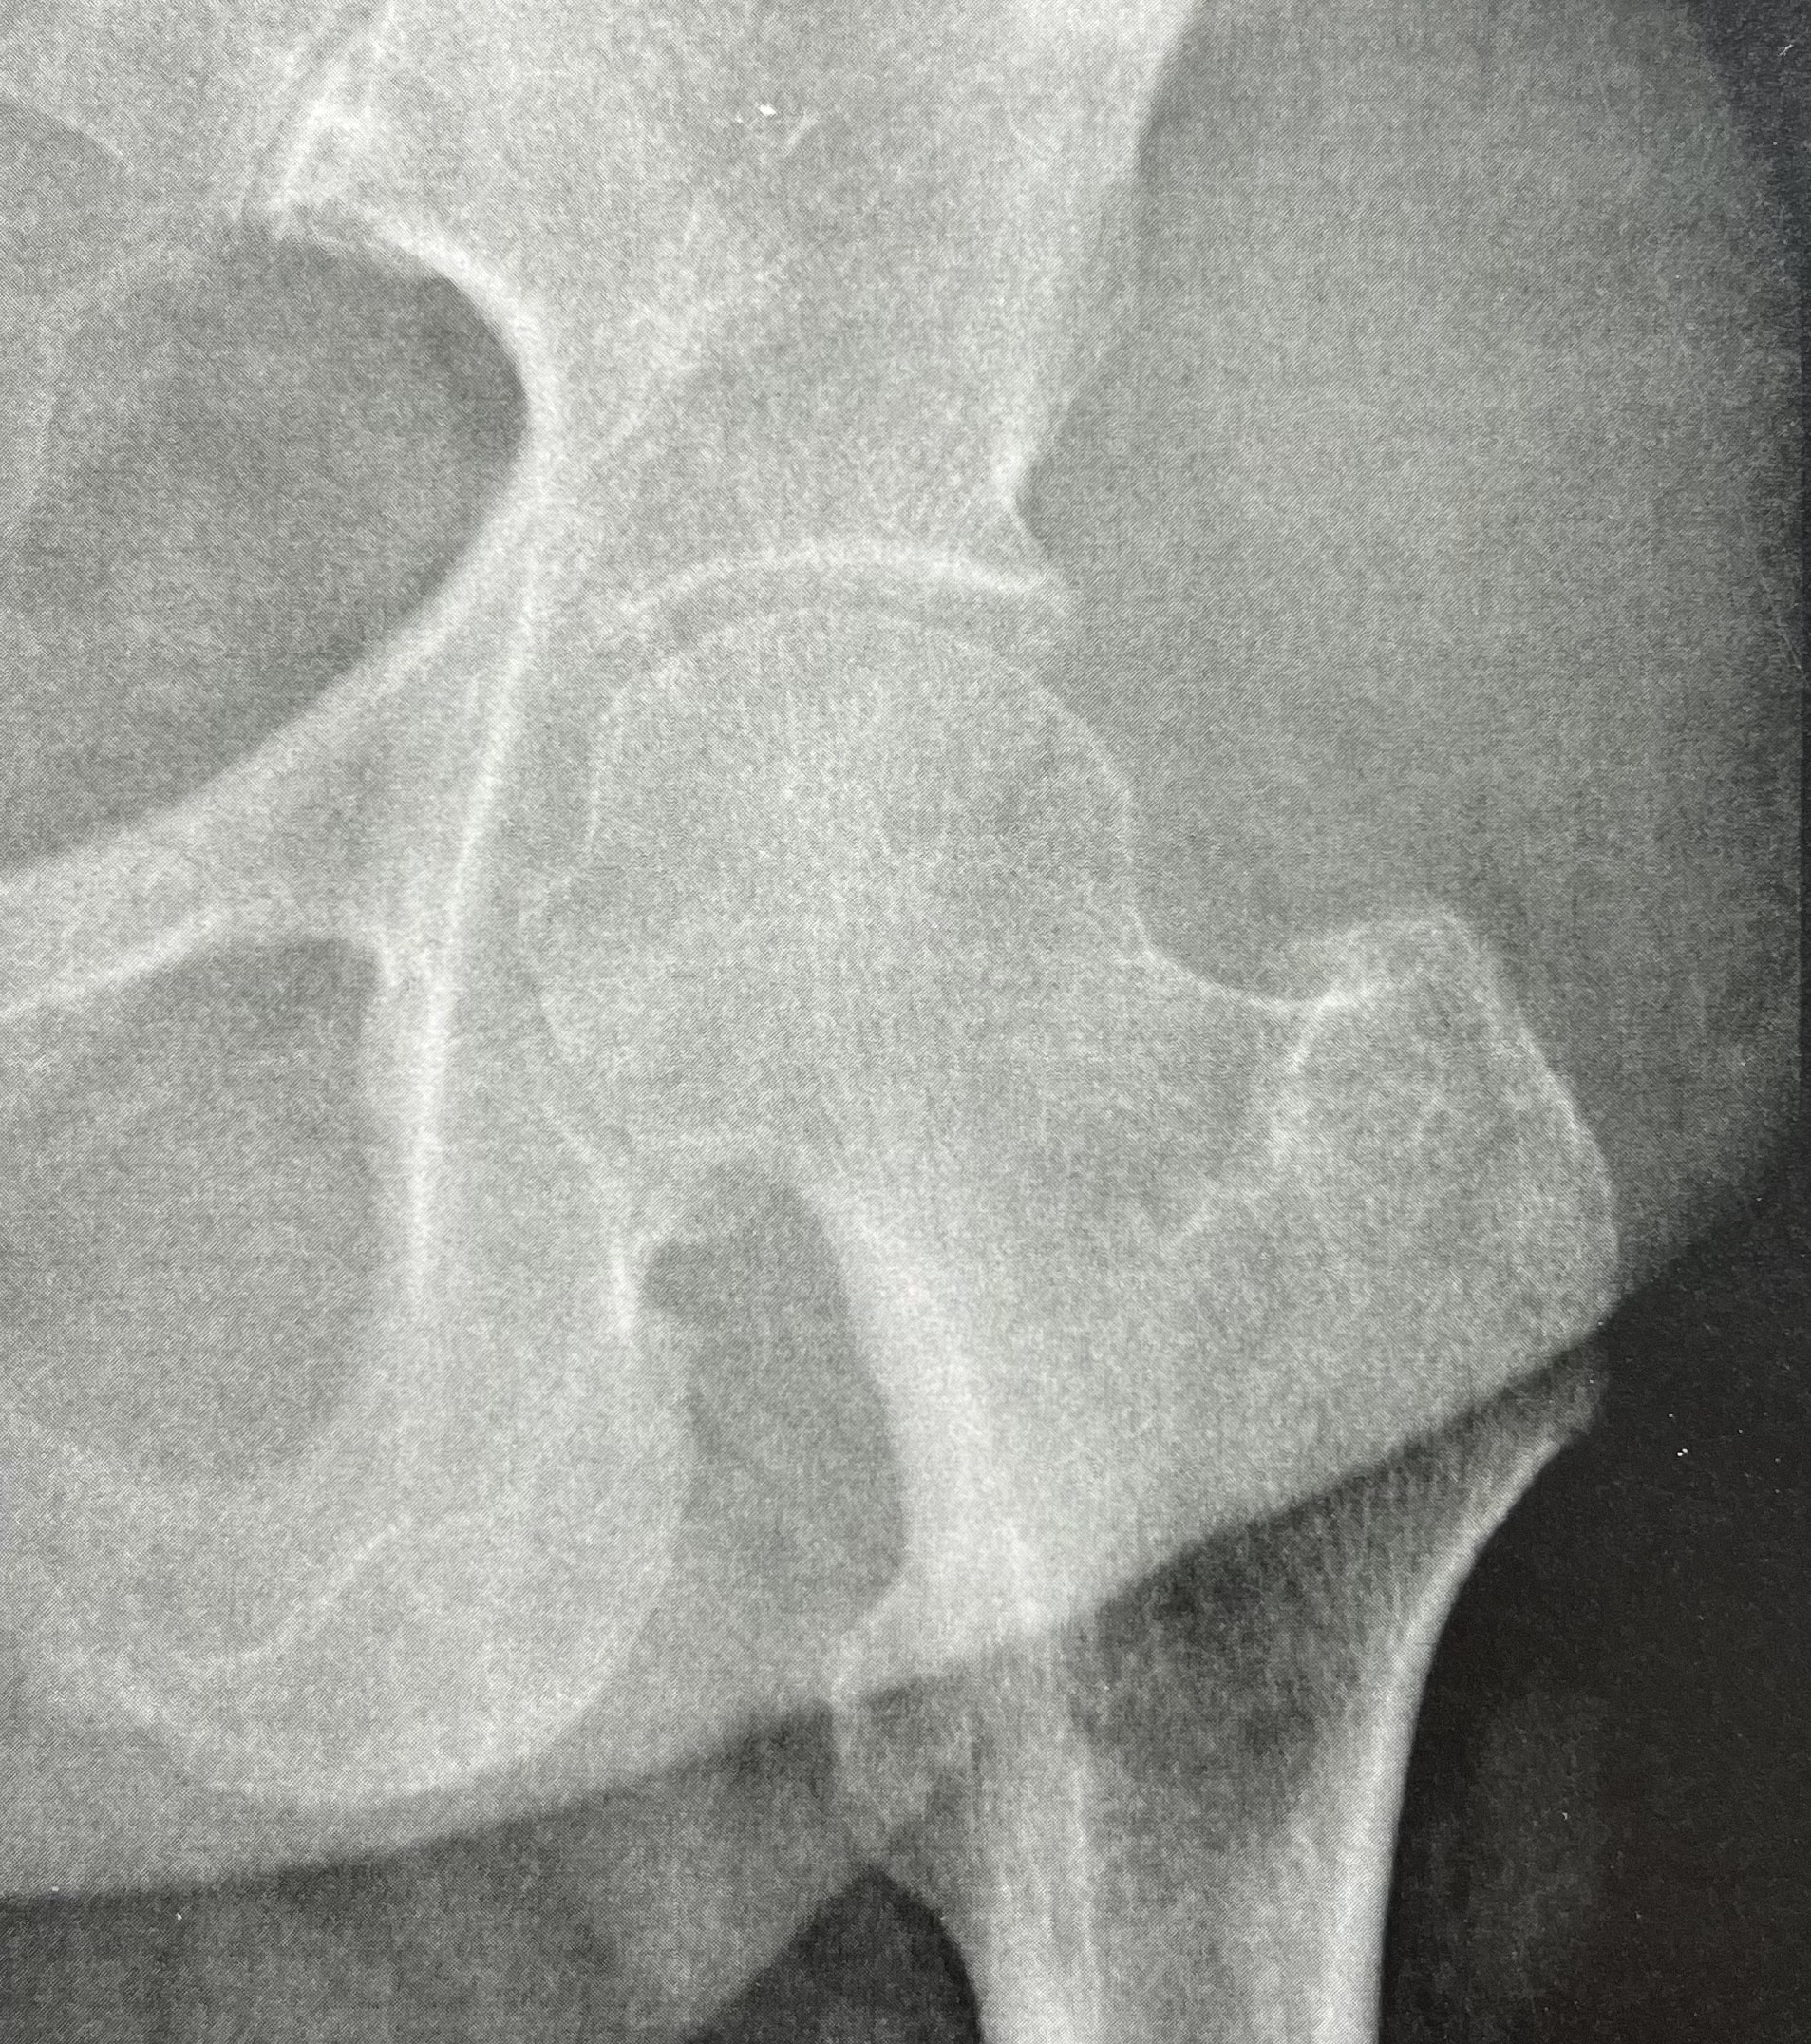

In some cases, patients present with mechanical hip pain despite perfectly normal radiographs.

When hip radiographs are strictly normal (no joint space narrowing, no osteophytes, no subchondral cysts, and no signs of osteoarthritis ) treatment is often limited to analgesics, anti-inflammatory drugs, and injections, and any surgical option is usually ruled out.

Thus, severe and extensive chondropathy may exist despite normal radiographs.